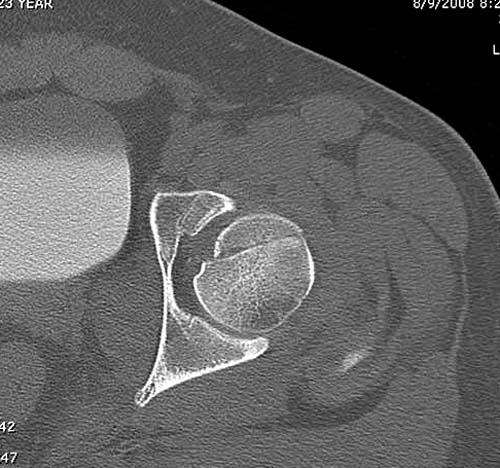

При сопутствующем переломе головки с ацетабулум, тогда артротомия из того доступа, который позволит фиксировать перелом впадины и фиксировать головку шурупами. На сегодня Headless Screw Synthes имеет преимущества перед другими, но при отстутствии их можно сделать обычными 3.5 мм., только головку надо утопить. При изолированном переломе доступ через trochanteric flip approach, который позволяет вывихнуть головку из ацетабулума и свободно работать без риска АВН. В вашем случае можно из переднего Smith Petersen доступа, потому что осколок спереди.

Представлены несколько вариантов фиксации: первый случай перелом головки с задним краем, операция из заднего доступа Кохер, а второй случай изолированный перелом головки - из трохантерного доступа.